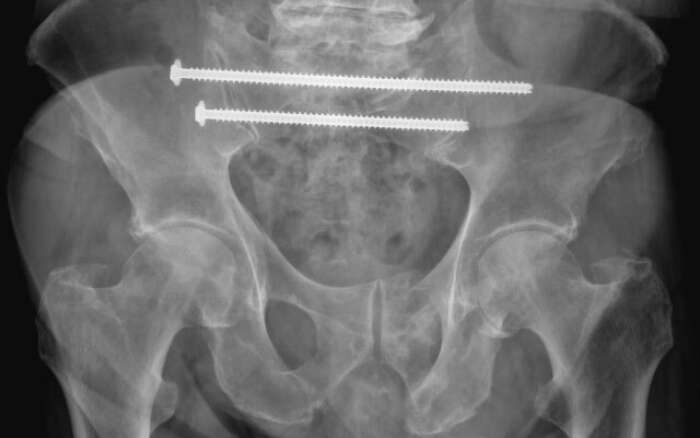

In diesem Beispiel war die Patientin vier Wochen nach einem Sturz nur noch mit Krücken und mit Schmerzen mobil. Die Computer Tomographie (CT) zeigte einen nicht verschobenen Bruch des Kreuzbeins und eine leicht verschobene Fraktur des Schambeins. Während der Operation implantierten wir CT-gesteuert zwei 7,3-mm-Schrauben. Die Schrauben gingen durch beide Ilio-Sakralgelenke und erste und zweite sakrale Wirbelkörper. Die Patientin konnte am nächsten Tag nach Hause entlassen werden und war schmerzfrei mobil.

Röntgen Becken nach Implantation zweier 7.3 mm Schrauben quer durch das Becken und Kreuzbein